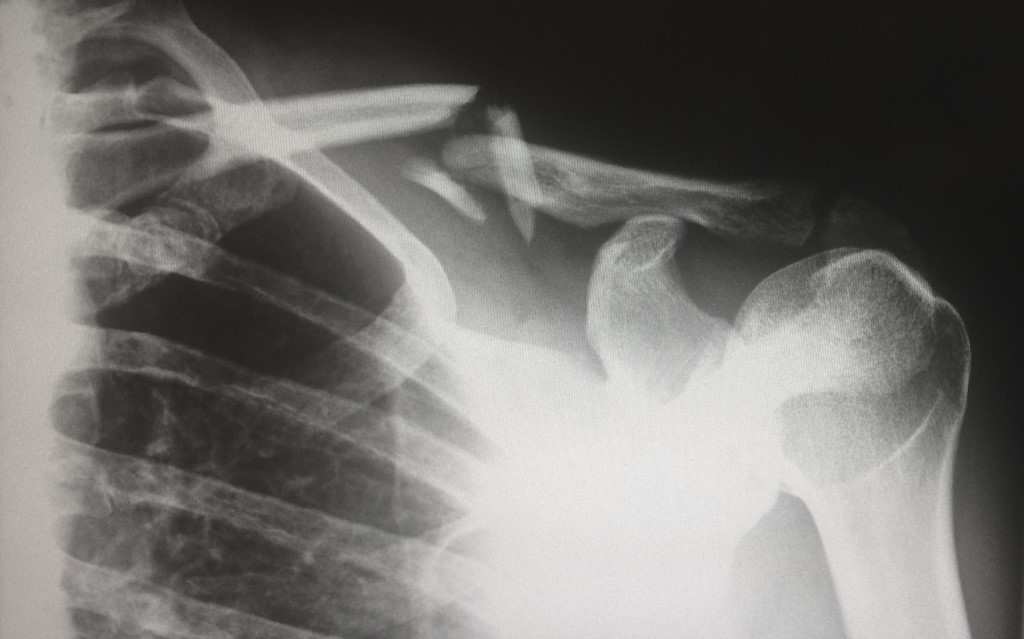

불안정한 상완와관절 (Glenohumeral instability)

재발성 탈구(recurrent dislocation)나 재발성 아탈구(recurrent subluxation)가 이 범주에 속하며, 대부분 외상 후의 불충분 한 치료에 의하나 때에 따라서는 외상의 기왕력 없이도 상완골두나 견갑와의 선천성 기형에 의하거나 Ehlers-Danlos 증후군, Mar fan 증후군 등과 같이 결체조직이 이완되는 질환에서 관절낭의 이완에 의해 발병한다.

재발성 탈구는 임상소견상 탈구를 분명히 알 수 있어 진단이 용이하나 재발성 아탈구는 진단에 어려움이 따른다. 환자는 평상 시 정상적으로 활동하다가 어떤 일정한 자세에서 갑자기 관절이 빠진 듯 느끼고 동통이 있으나 곧 정상으로 돌아가고 이러한 일 이 반복하여 일어난다. 이학적 소견상 관절의 운동은 정상이나 인위적으로 힘을 가하여 관절을 아탈구되는 방향으로 전위시키려 하면 환자는 갑자기 불안해한다.(apprehension test)